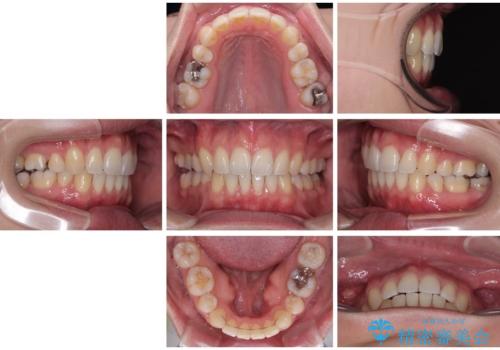

口元が出ているのが気になる。審美装置による抜歯矯正

- 口元の突出感と下の前歯のがたつきを主訴として来院された患者様です。

口元の突出感と叢生改善のため上下左右の第一小臼歯4本を抜歯し、ワイヤー装置にて矯正治療を行うこととしました。

なるべく目立たない装置が希望だったため、審美装置で治療を行いました。

左上はアンカースクリューを併用することでスムーズに抜歯スペースを閉じることができました。

口元の突出感もなくなり満足されました。